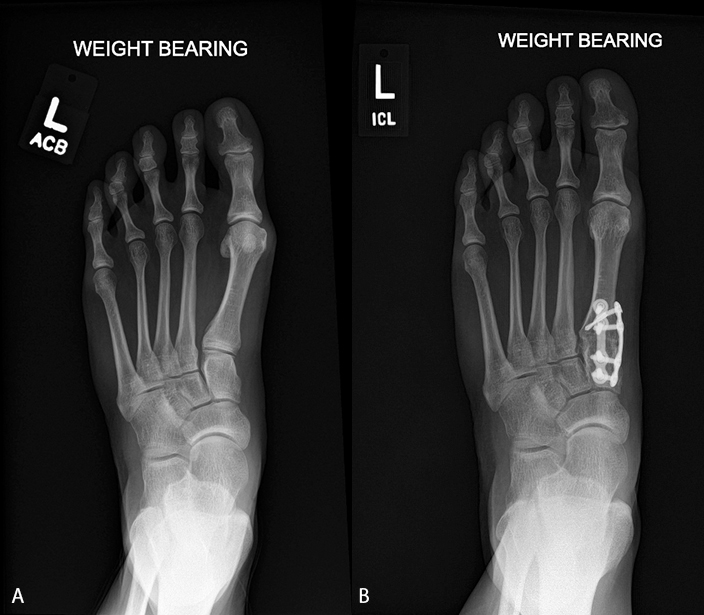

From www.lapiplasty.com

Treatment of Hallux Valgus Deformity Benefits from 3D ‘Revolution’ Treace What Is The Best Treatment For Hallux Valgus Radiographs of the foot are. Nonsurgical treatments that may relieve the pain and pressure of a bunion include: A bunion is a bony bump that forms on the joint at the base of your big toe. Use warm soaks, ice packs, whirlpool, ultrasound and massage. Treatment for hallux valgus ranges from conservative to surgical management. There are about 131 different. What Is The Best Treatment For Hallux Valgus.